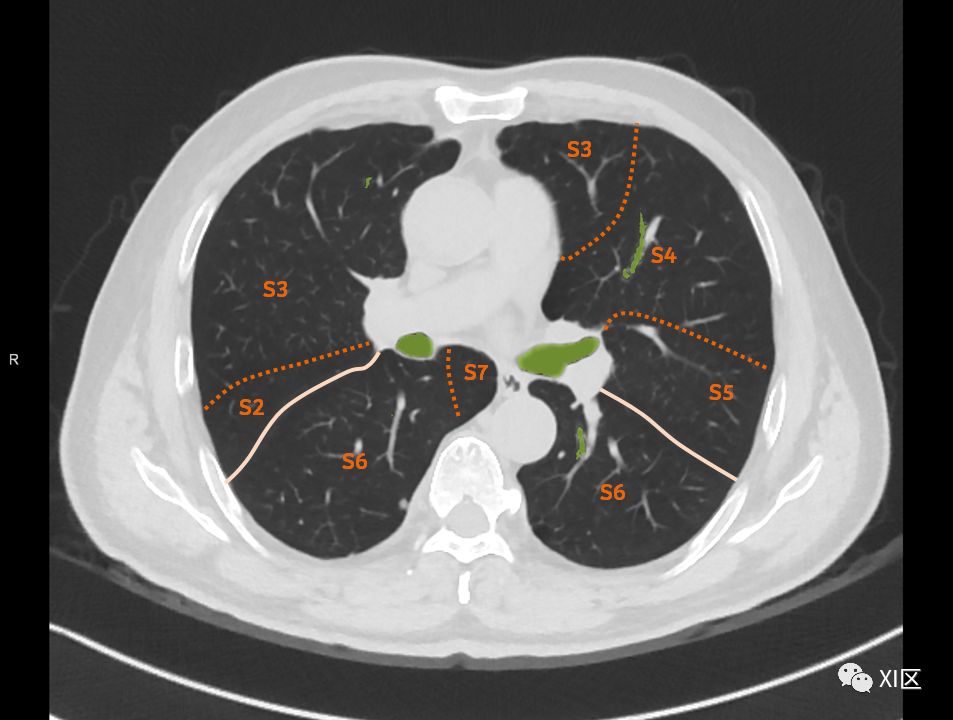

在进行肺的分段时,可以上下观察浏览,沿着相应气管的走形可以更容易准确地进行分段。

肺的分段

肺的断层分段示意图